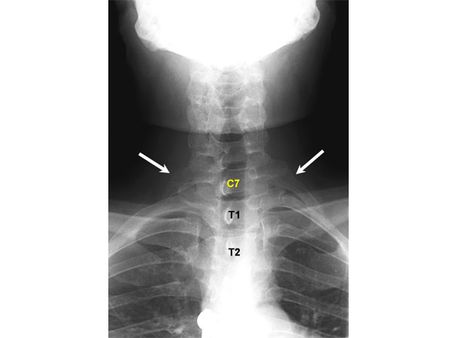

Additional Ribs

This is one of the rarest conditions that are found mostly in women. The size of the ribs can vary from small to full-grown, and according to studies they are known as cervical ribs. These ribs are located near the cervical spine area.